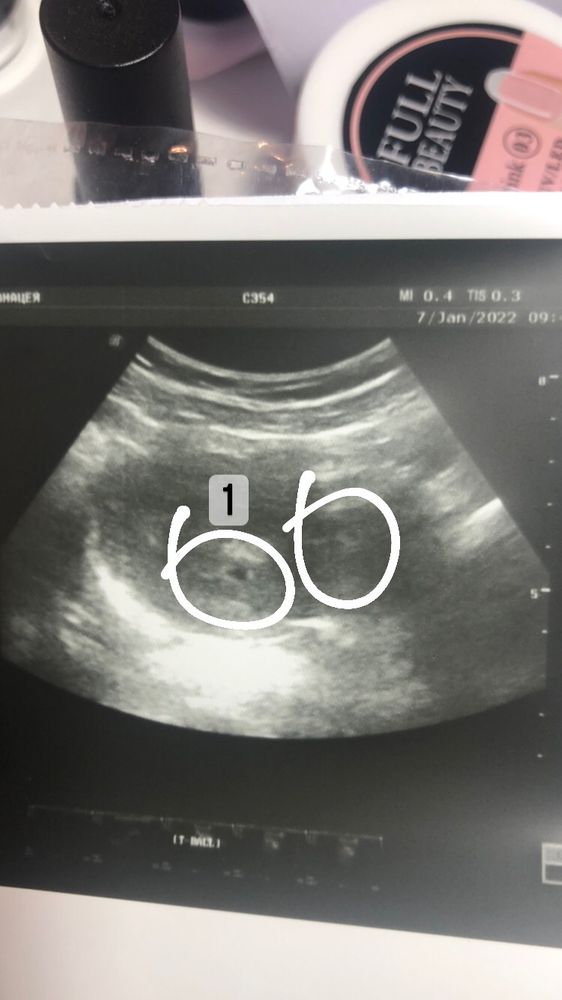

Двойня ?

Подскажите пожалуйста ,это может быть двойняшки ?

Узист сказал что матка расширена не на свой срок, больше

Срок 3-4 недели ,может кто сталкивался с таким

Сказал прийти на приём через 2 недели ,но за многоплодную беременность не сказал ничего 🤔